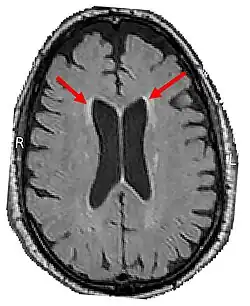

LENAS is seen with damage to the white matter and axons within the brain. The external human LENAS brain shows findings in several major structures. There is mild atrophy of the frontoparietal regions of the brain and a mild reduction of the thalamus and rostral (front) part of the caudate nucleus (which is located in an area of the brain called the basal ganglia).[5] Abnormalities in the frontal, frontoparietal, and temporal lobes are most severe and predominant with LENAS and asymmetry of the cerebral hemispheres has sometimes been found.[5] LENAS also may show moderately enlarged lateral ventricles and atrophy in corticospinal tracts as well as in the pons.[5]

- Longitudinal MRI studies annually can potentially also help with prognosis. This was found from another study which found that, as throughout the disease course, the more rapid the confluence of patchy or focal T2-weighted hyperintensities and the progression of cortical atrophy suggests the poorer the prognosis appears to be.[13][14][12]